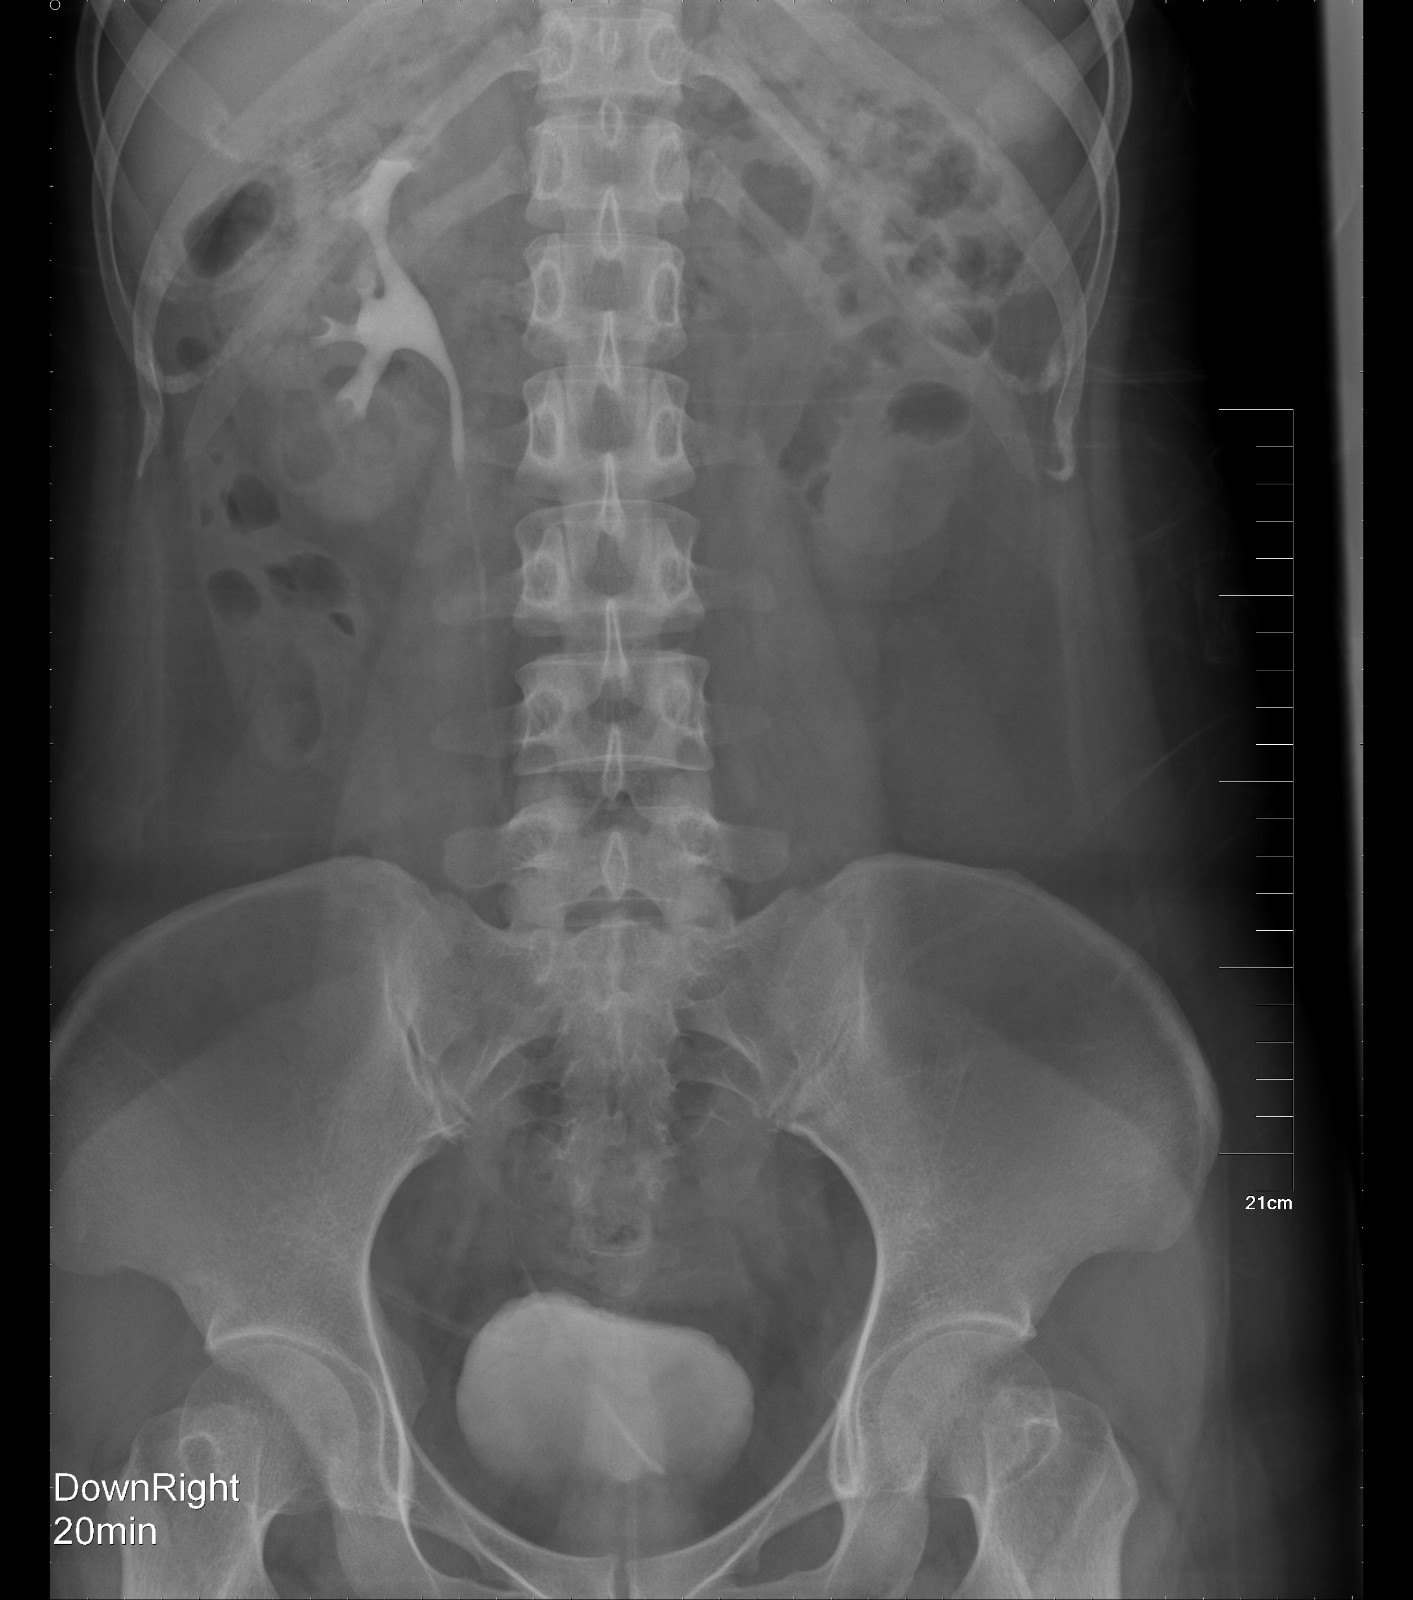

KUB提示右输尿管下段结石呈石街样排列,引起右输尿管完全梗阻,导致右肾萎缩

2016年04月手术患者,女性,32岁,昆山人,五年前曾因右输尿管结石引起肾绞痛于当地消炎补液解痉排石处理,疼痛缓解后未于重视,其间从未予复查,2周前出现右腰痛,与当地诊所就诊后予以震波碎石无效,并出现发热,急诊来我院就诊,CT:右肾萎缩,右侧肾脏积水,右侧输尿管多发结石形成石街约4.5*1.5cm,GFR:右侧17.2ml/min,左侧43.2ml/min。因左侧健肾代偿,肾功能正常:Cr 132umol/L;术前诊断:右输尿管下段多发结石 右肾萎缩 肾功能不全,鉴于右输尿管结石梗阻时间太长,肾功能不全,已处于失代偿期,最终也只能行右侧输尿管下段切开取术,解除输尿管下段梗阻,尽可能保护已经萎缩的肾脏,该患者预后不良。